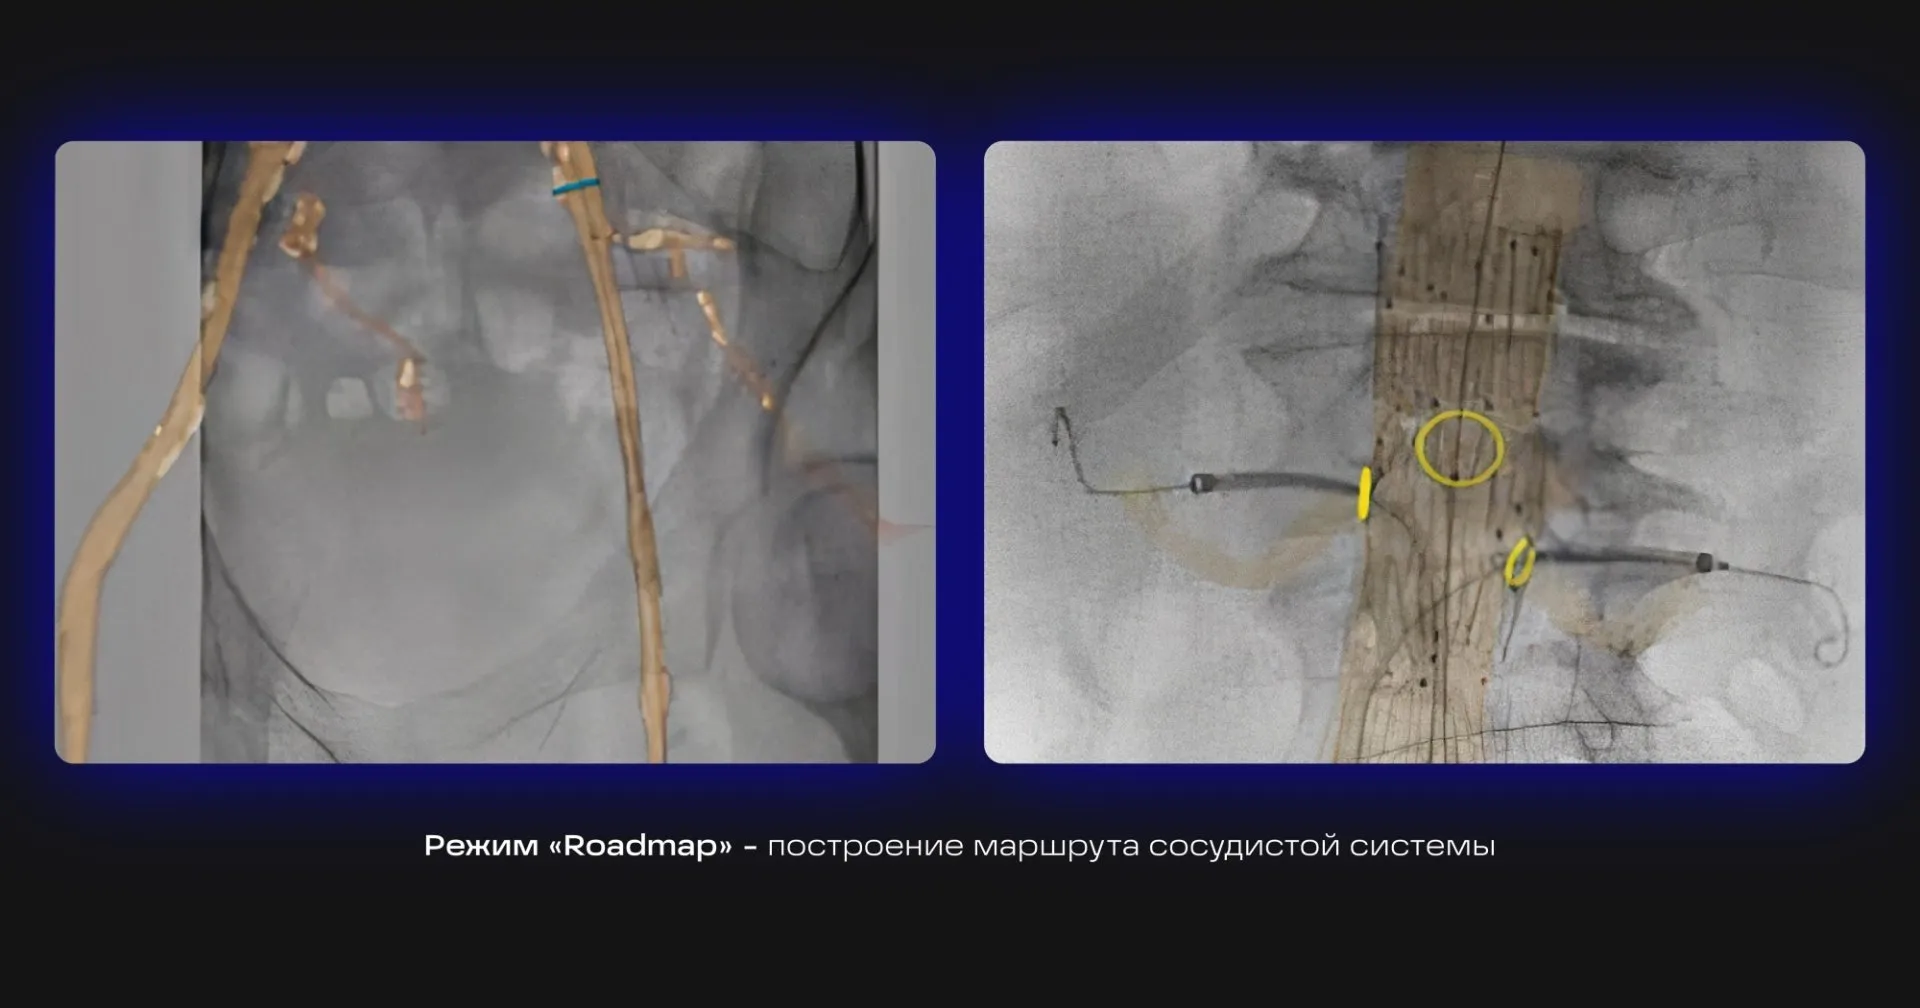

Режим «Roadmap» — построение маршрута сосудистой системы на «живом» изображении в реальном времени для навигации проводника.

Клинические изображения_2.jpg